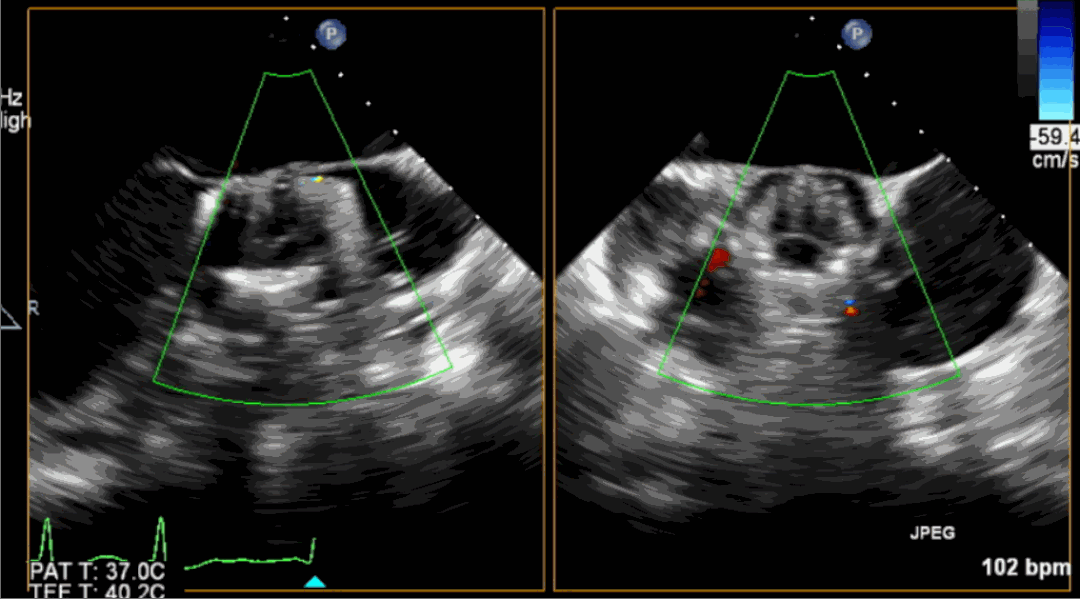

術中釋放定位鍵后DSA影像圖

術中瓣膜釋放過程

術后超聲影像圖

手術采用經心尖入路,對患者進行全麻后,在左側心尖處做3-4cm微創手術切口,在DSA及超聲引導下手術順利完成。從導入器械到完成瓣膜置入,僅耗時約10分鐘。術后即刻主動脈瓣返流程度由術前大量返流轉為消失,患者于導管室拔除氣管插管,次日由ICU轉入普通病房。